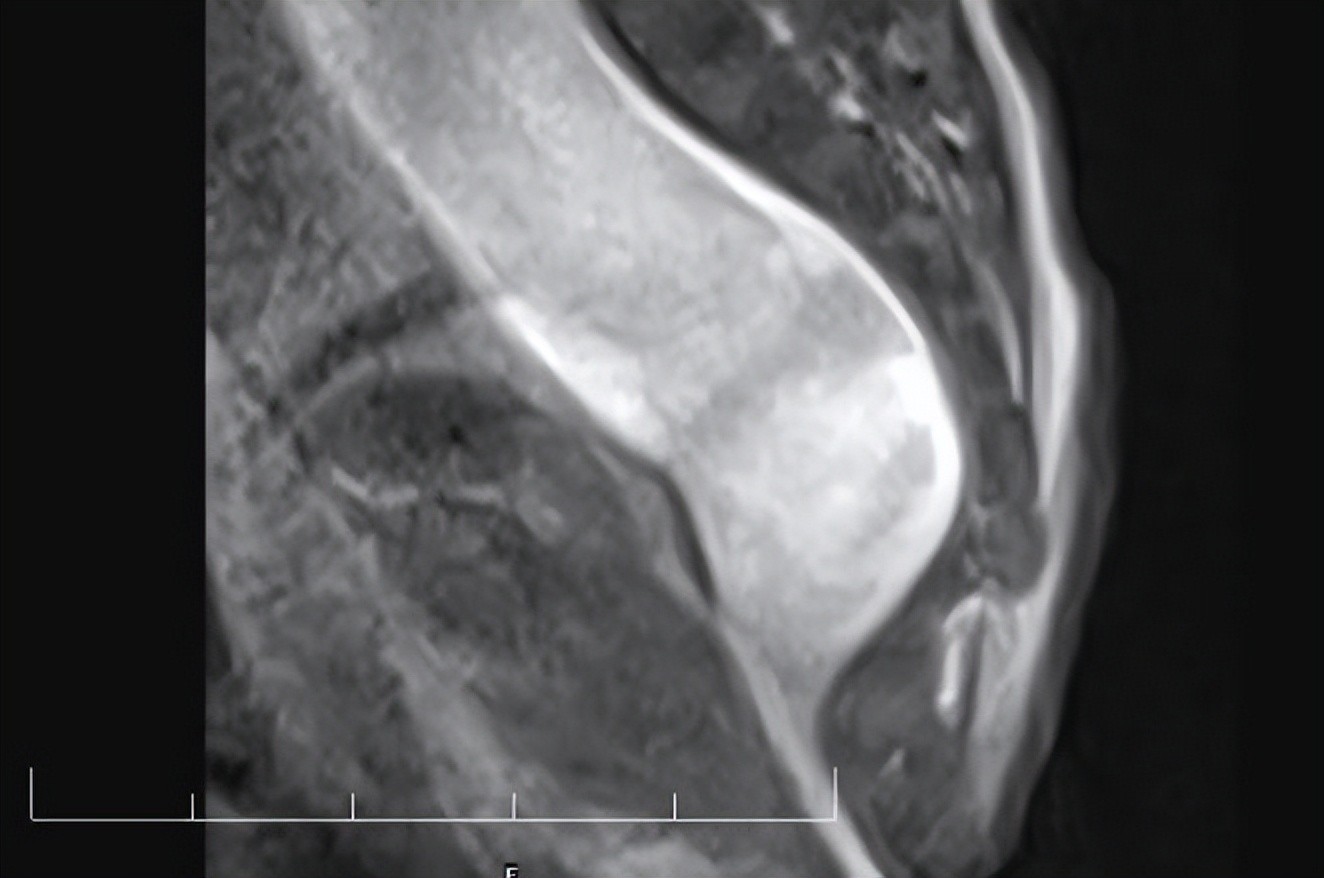

(患儿侧卧位造影图)

麻醉手术部唐岩峰主任表示:“这次手术的第一大难关就是“呼吸关”,因为术中采用“俯卧位气管插管”体位,所以气道管理很重要,要防止气管导管的脱位、意外脱出,这对麻醉师的要求非常高。